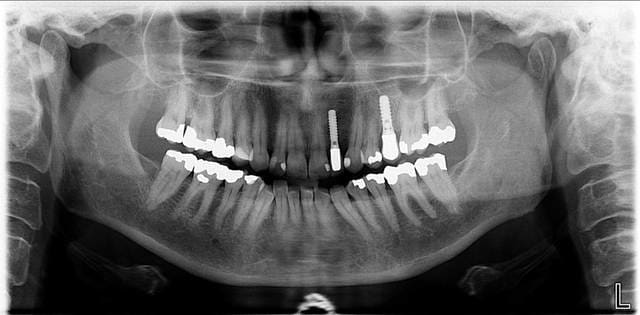

voici celle d'instrumentarium

Opt op100d rf2enk - Eugenol

Opt op100d pk9hv4 - Eugenol

justement domi38 la différence entre les bons et les moins bons se fait dans la zone antérieur, mais je te rassure, il apparait que le plan meca est tres bon aussi,

le choix peut se faire sur l'irradation , exemple le sironna est un de ceux qui irradie le plus

et l'instrumentarium le moins ...

a vous de savoir ce qui est le meilleu rpour vous et pour vos patients